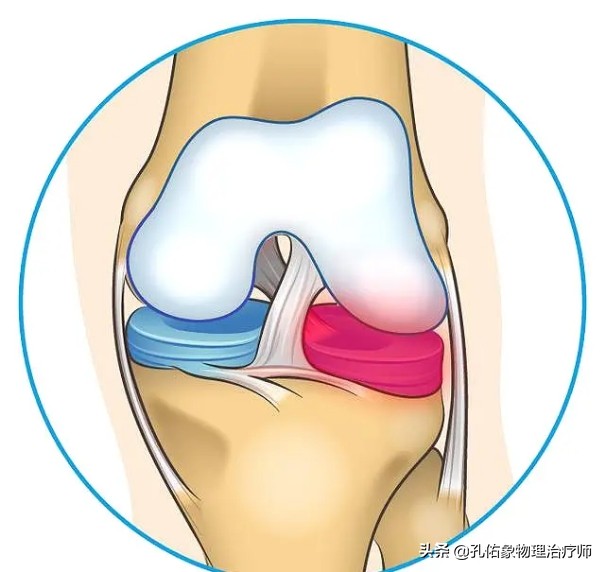

它位于膝关节大腿骨和小腿骨的软骨面之间,半月板在膝关节的内外侧各有一块,它是纤维软骨。其表面是非常光滑的,有一定的弹性。在膝关节屈伸活动的时候,可以帮助膝关节更好的匹配自由运动;同时增加了胫股关节之间的接触面积,减少局部的压力而分担身体的负荷,减少了大腿骨和小腿骨上关节软骨在膝活动时候所承受的摩擦,起着保护膝关节稳定的功能。

如上图所示,是膝关节水平面从上往下看的一个剖面图,前方有前交叉韧带,后方有后交叉韧带,在胫骨平台里面有内侧的半月板和外侧的半月板,前方称为半月板的前角(绿色),后方称为半月板的后角(紫色),不管是内侧半月板还是外侧半月板都有前后角,连接前后角的中间部分是半月板体(红色);所以经常会在膝关节损伤时拍核磁共振显示:半月板的前角损伤,后角损伤或是撕裂,指的就是这些地方,在您脑子里就会有这个映像,因为半月板是我们没办法去用手可触及到的,在外观上,我们也不能用肉眼去看到。